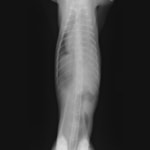

術後レントゲン

腹部臓器が腹腔内に戻り、腹部と胸部の境界および心臓や肺の陰影が明瞭に見えるようになりました。